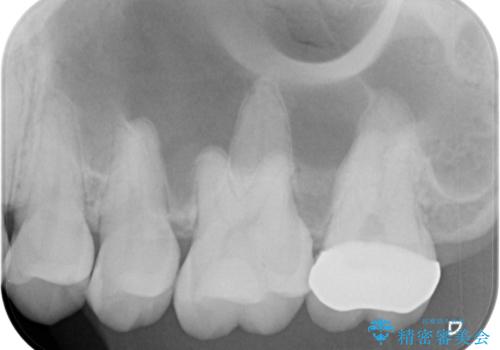

- 大学病院で「詰め物の下に虫歯がある」と言われたことを主訴に来院された患者様です。たまにしみる感じがするとのことでした。

レントゲン上で詰め物とご自身の歯の間に隙間を認めました。

拡大鏡視野下で詰め物と虫歯の除去を行い、詰め物の範囲が大きかったためオールセラミッククラウンに適した形に整えました。